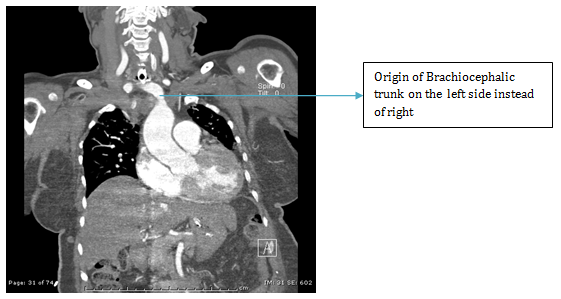

ENT referral was sought and a colour Doppler was advised which showed an abnormal large artery in running across in front of the Trachea. A CT angiography was then done which revealed anomalous Brachiocephalic trunk running from left to right across in front of the trachea which had pushed the thyroid gland to the level of Cricoid cartilage (Figures 1-4).

Figure 1 Angiogram.

Figure 2 Angiogram.

Figure 3 Angiogram

Figure 4 VRT, CT Angiography